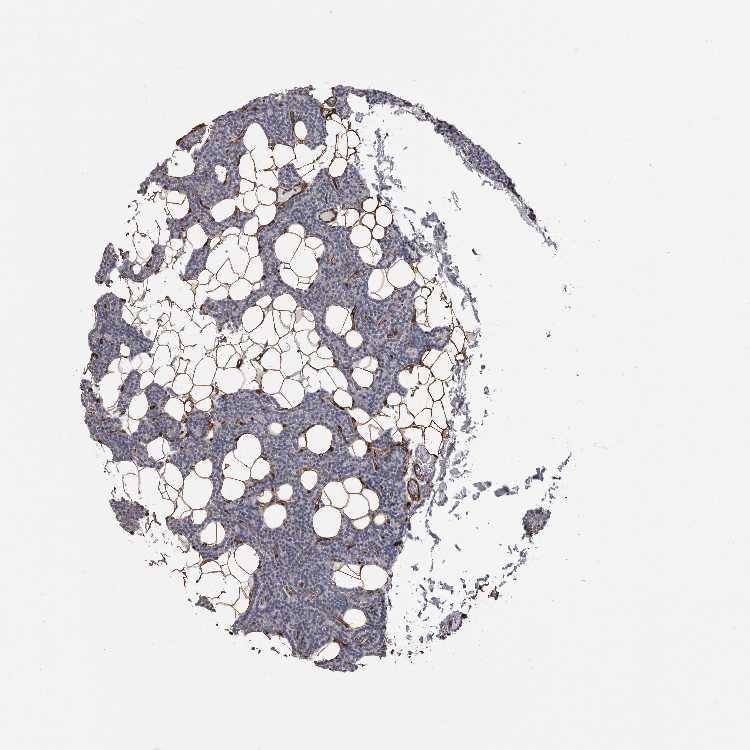

TISSUE PRIMARY DATA PARATHYROID GLAND Show tissue menu

Parathyroid gland

PARATHYROID GLAND - Expression summary

PARATHYROID GLAND - Antibody stainingi

Antibody staining in the annotated cell types in the current human tissue is reported as not detected, low, medium, or high, based on conventional immunohistochemistry profiling in selected tissues. This score is based on the combination of the staining intensity and fraction of stained cells.

Each image is clickable and will lead to virtual microscopy that enables deeper exploration of all samples and also displays staining intensity scores, fraction scores and subcellular localization as well as patient and tissue information for each sample.

Antibody HPA000980Antibody CAB025797

Glandular cells Not detectedNot detected